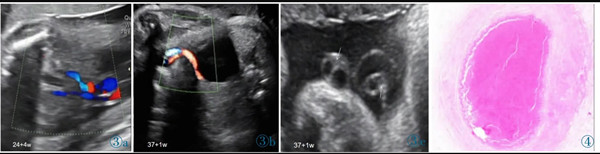

11 例中孕期超聲均可見2 條UA(膀胱水平橫切面顯示2 條UA 血流信號),超聲最后一次提示可見2 條UA 的平均孕周為(31.2±3.1)周。11 例超聲首次提示UA 數(shù)目異常(表現(xiàn)為膀胱水平橫切面UA彩色多普勒僅顯示1 條UA 及血流信號,另一側(cè)血流信號消失)的平均孕周為(36.7±2.8)周,6 例(54.4%)為膀胱左側(cè)血流信號消失,5 例(45.5%)為膀胱右側(cè)血流信號消失。7 例(63.6%)孕晚期超聲首次即提示單條UAT,這7 例臍帶游離段橫切面二維灰階圖像均顯示3 個管腔結(jié)構(gòu),其中1 條UA 內(nèi)可見稍高回聲填充且血流信號消失(圖1);1 例(9.1%)在孕34+4周提示單臍動脈,在孕37 周超聲隨訪中糾正診斷為單條UAT,因超聲提示臍帶高度螺旋,且在臍帶橫切面下見臍靜脈呈“C 形”包繞2條UA,1 條UA 內(nèi)存在血栓回聲(圖2),該病例同時合并胎兒生長受限;3 例(27.3%)整個孕期均提示單臍動脈,回顧其既往中孕期超聲均見2 條UA,晚孕期超聲發(fā)現(xiàn)1 條UA 內(nèi)存在血栓回聲(圖3)。

圖3 誤診為單臍動脈病例的超聲圖像。圖3a:孕24+4 周,膀胱兩側(cè)均可見UA 血流信號;圖3b:孕37+1 周,膀胱一側(cè)UA 血流信號消失;圖3c:臍帶橫切面見臍靜脈呈“C 形”包繞2 條UA,箭頭所示其中1 條UA 管腔細(xì)小,內(nèi)為稍高回聲(血栓)填充。圖4 臍帶病理(HE 染色)。UA 內(nèi)見血栓形成,管壁彈力纖維梗死。Figure 3.Ultrasonography misdiagnosed as single umbilical artery.Figure 3a: At 24+4 weeks,the blood flow of two UAs is seen in both sides of bladder.Figure 3b: At 37+1 weeks,only one UA is seen in the level of bladder.Figure 3c: In the cross section of umbilical cord,two UAs are surrounded by umbilical vein.As indicated by the arrows,one UA has smaller lumen which is filled with a slightly higher echo(thrombi).Figure 4.The pathological finding of umbilical cord (HE stain).The UA lumen is filled with thrombi.The necrosis of elastic fibers are found in arterial wall.

產(chǎn)時肉眼可見11 例臍帶長度均正常,其中4 例(36.4%)臍帶高度螺旋,1 例(9.1%)帆狀胎盤。7 例產(chǎn)時病歷描述可見1 條UA 外觀全程/部分呈暗紅色,1 例UA 部分呈土黃色,橫斷面均可見血栓形成。3 例病歷資料中未描述臍帶外觀。病理結(jié)果提示11 例臍帶橫斷面均提示有2 條UA,鏡下所見其中1 條UA 內(nèi)血栓形成(圖4)。